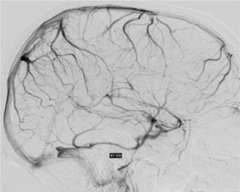

Cerebral venous sinus thrombosis is a rare condition when a large blood clot forms in a large vein in the brain called a dural venous sinus. The clot blocks the dural sinus and prevents the blood flow draining from the brain (Figure 1).

Brain imaging studies such as MRI and CT are commonly used to demonstrate the clot in the cerebral venous sinuses. If necessary, catheter angiography is also performed to visualize the relatively small clots or when catheter based clot-removing treatment is needed (Figure 1).